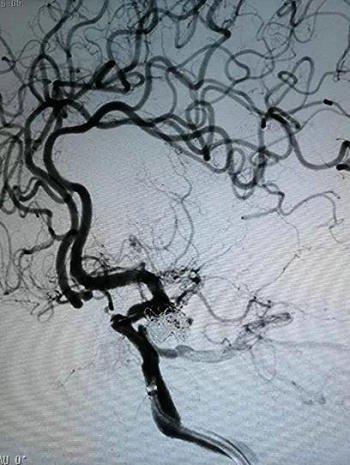

选好手术方案后就开始行动,在血管外科崔文军副主任的协助下,顺利暴露颈总动脉,预留打结线,穿刺进入颈总动脉,指引导管顺利进入颈内动脉,支架辅助行后交通动脉瘤栓塞,1小时后手术结束,排雷成功,导管退出后预留线打结,颈动脉穿刺缝合处无明显渗血,手术成功!患者很快清醒过来,顺利返回病房。经过一段时间的治疗,郭奶奶颅内的蛛网膜下腔出血也已吸收,没有致残,没有留下后遗症,整个人神清气爽,出院回家了。

支架辅助栓塞后交通动脉瘤

支架辅助后交通动脉瘤栓塞,排“雷”成功